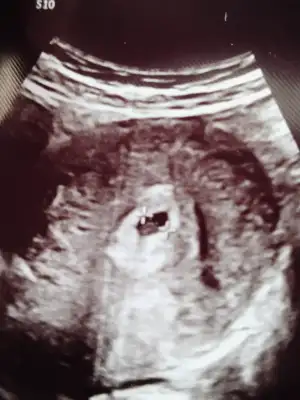

39

Merhaba anneler 6+3haftalik hamileyim bugün ilk ultrasyon muaynem vardı ama doktor haftama göre kesemin küçük olduğunu söyledi içinde bebek oluşmaya başlamış ama küçük olduğu için kalp atışını duyamadım kesenin büyüklüğü 7mm dedi bu bir sıkıntımı çok üzgünüm şu an başına gelen yada bilgisi olan varmı

Benim kese 6.93mm çok küçük geç dollenmemi acaba dedi ama işte net bişey söylemedi

Şimdi geldim 6+5 dedi fakrli Dr gitmiştim kendi Dr yoktu oynama olur dedi sorun değil daha küçük haftasını hesaplama net olmaz dedi duyduk kalp atışını sorun yok şükür farklı oluyor her cihaz Dr onu anladim

Dediğin gibi oldu bugün doktora gittim çok şükür kese büyümüş ve kalp atışını duydum ama regli tarihime göre 7+5 olması gerekiyo 6+5 dedi doktor geç döllenme olduğu için herşey normal 15 gün sonra görüşürüz dedi

Geç dollenmeymis bugün kalp atışını duyduk çok şükür regla göre 7+5 olması gerekiyo ama ultrasyon 6+5 gosteriyo